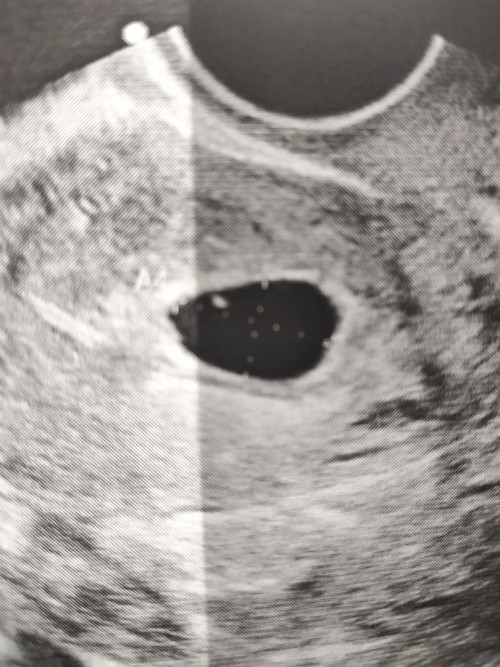

เจอแต่ถุงตั้งครรภ์

วันนี้ไปซาวหน้าท้อง เจอแต่ถุงตั้งครรภ์ไม่เจอตัวอ่อน ถ้านับตามประจำเดือนอายุครรภ์ 10 สัปดาห์แล้ว หมอนัดซาวอีกครั้งวันที่ 12 กุมภา แม่กลัวเป๋นท้องลมมากๆ มีใครเคยเจอเคสแบบนี้ไหมคะ